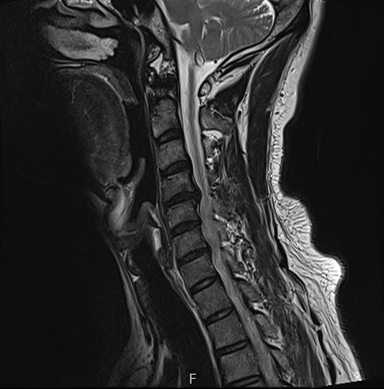

검사 결과는 예상대로였어요.

목디스크와 협착증이 함께 있었습니다 ㅠㅠ

그림6.png

<Fig 1. 목 디스크 및 협착증으로 진단된 MRI>

보이시나요?

디스크가 튀어나와 신경을 누르고 있었고, 협착까지 동반되어 있는 상태…

환자분께 영상을 보여드리며 설명을 드렸는데요.

목에서 문제가 생기면 어깨 쪽으로

통증이 퍼져나가는 경우가 정말 많다는 점을

눈으로 직접 확인해 보니 이해가 된다는 표정이셨어요.